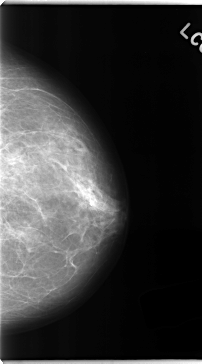

C_0149_1.LEFT_MLO

LEFT_MLO LINES 4752 PIXELS_PER_LINE 2464 BITS_PER_PIXEL 12 RESOLUTION 50 NON_OVERLAY